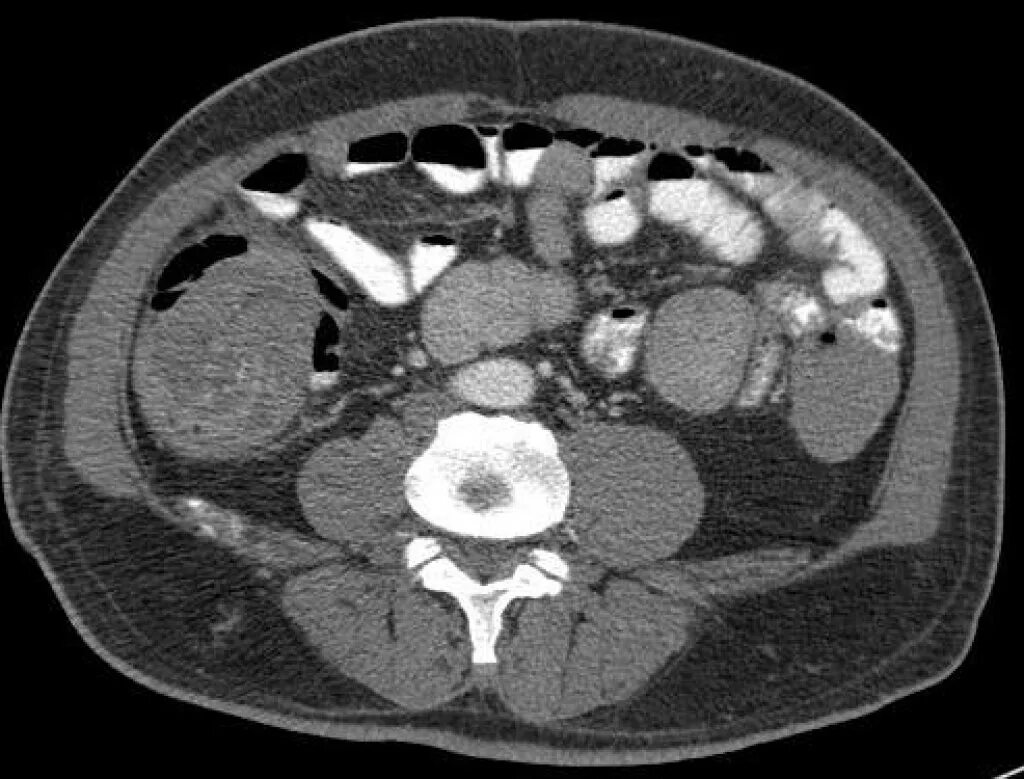

Метастазы при раке сигмовидной кишки